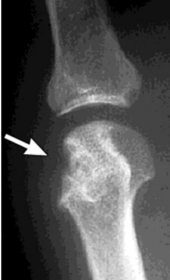

| What disease is this? What does the arrow indicate? | Rheumatoid arthritis. Arrow = Bone erosion secondary to inflammation of retrocalcaneal bursa. |